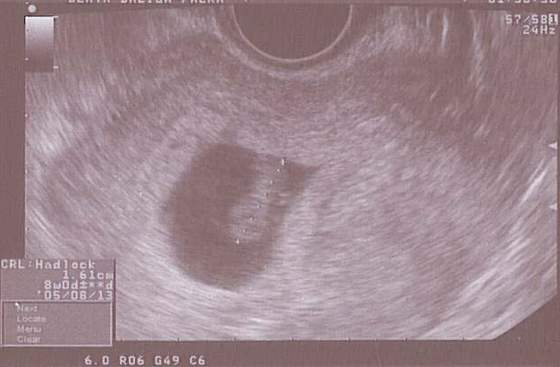

teraz w 4 tyg 4 dniu było 3,5 mm ale na szczęście wydaje mi się że to jeszcze norma

W 4. tc liczac od OM?! To olbrzymi zarodek!